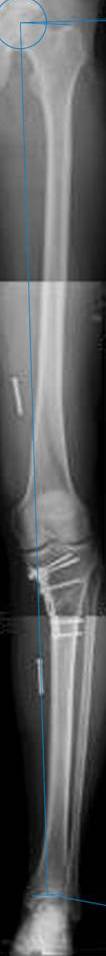

картинки оперированного пациента 40 лет, травма в 2006 году.

оперирован 06.11.2009г - корригирующая остеотомия большеберцовой кости.

Я картинку собрал с некоторыми погрешностями, если провести отвес от центра вращения головки бедра до середины голени (на пациенте),то имеется небольшой вальгус (гиперкоррекция)конечно она (гиперкоррекция) не достигает 10 гр, но 5 гр она достигает.

К сожалению, не очень удачный пример. Если верить Р-граммам, имеет место быть дисплазия мыщелков бедренной кости с наклоном суставной линии. Это уже создает сложности получения хороших отдаленных результатов. Кроме того, по классике, необходима гиперкоррекция с созданием вальгуса 7-10 градусов для максимальной разгрузки медиального отдела КС. Если верить укладке, то линия сустава имеет четкий варусный наклон, поэтому результат операции м.б. кратковременным. В этих случаях показана двойная остеотомия бедра и тибии.

Если сделать правильно, то видно, что бедренная кость в порядке, а цель остеотомии (низкой, кстати), не достигнута вовсе.

Сохраняется варус. Для того, чтобы создать вальгусную гиперкоррекцию, не моделируя при этом откровенный Х голени, можно сделать медиализирующую остеотомию.

Ув.Александр.Как раз бедренная кость и не в порядке. Абсолютно прав проф.Р.М.Тихилов - "имеет место быть дисплазия мыщелков бедренной кости с наклоном суставной линии". Именно это определяет патомеханику процесса в суставе и пути её устранения. Тибиальная остеотомия - палеотив, ещё менее эффективна медиализация. Только двойная(или на двух уровнях) остеотомия исправит положение сустава и при данном (рентгенологическом) состоянии сустава, протез понадабиться глядишь лет через двадцать, а может вообще не понадобиться.